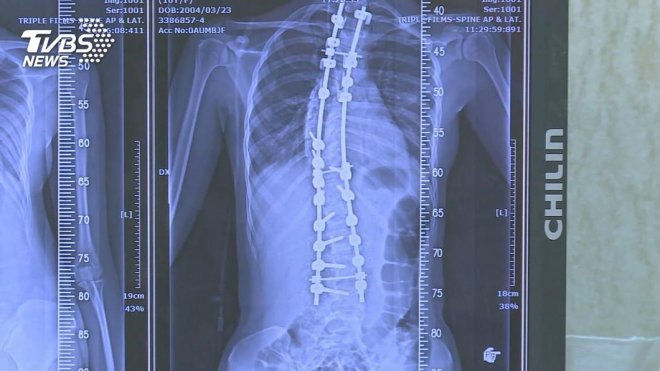

醫生開給他藥物治療,並要求配合復健,預計要三個月以上時間,才能漸漸恢復神經功能。翹腿,其實是不良姿勢,上方膝蓋疊在下方膝蓋並施加壓力,膝蓋扭轉成不自然角度,增加膝關節壓力,翹腿時單側大腿上抬,同側骨盆也跟著旋轉抬高,下背部脊椎也容易代償側彎。

因此,翹腳容易造成下背痛、下肢循環不良,也會衍伸出骨盆傾斜、脊椎側彎、增加罹患退化性關節炎風險,此外,翹腿也會使椎間盤單側受力,當椎間盤受到不平衡壓迫時,長期下來可能會導致「椎間盤突出」!若忍不住非要翹腳,最好不要超過5分鐘,而且要變換坐姿。